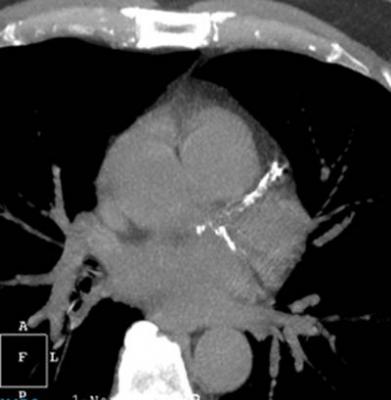

Photo 1, showing a coronary CT angiography scan of a heavily calcified coronary artery. Photo 2 shows the corresponding CT-FFR.

Photo 2, showing HeartFlow's CT-FFR report for the same vessel segment as shown in Photo 1.